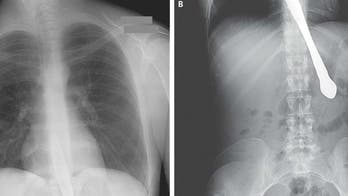

June 12, 2015 Outrageous injuries The next time you complain about a paper cut or headache, consider these injuries